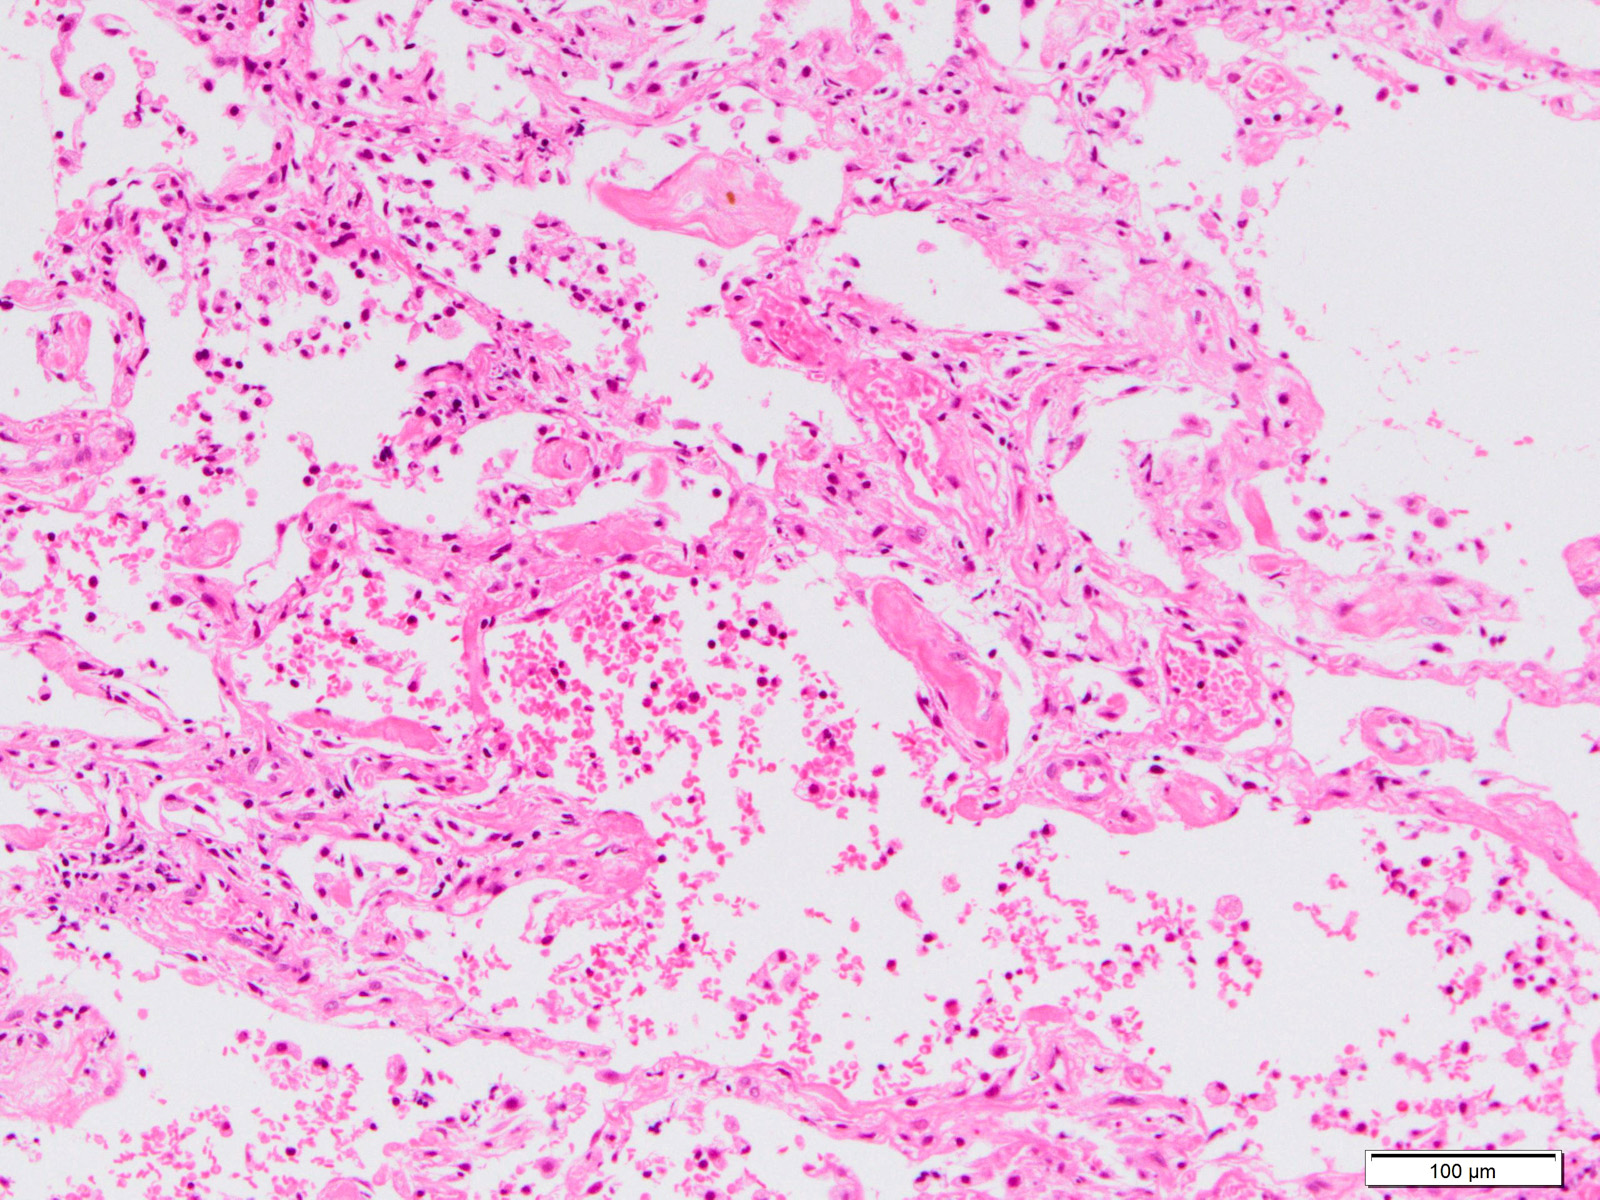

Microscopic (histologic) description

- Histopathology of DAD progresses from exudative (acute) phase through proliferative / organizing (subacute) phase to chronic fibrotic phase roughly corresponding to the period of ARDS (Am J Pathol 1976;85:209, Arch Pathol Lab Med 2010;134:719, Clin Chest Med 2000;21:435, N Engl J Med 2000;342:1334)

- Exudative (acute) phase

- Alveolar change

- Hyaline membranes on alveolar duct or sacs

- Interstitial and intra-alveolar edema

- Collapsed alveoli

- Epithelial change

- Denudation and necrosis of type I pneumocytes

- Vascular change

- Necrosis of endothelial cells

- Neutrophil aggregation

- Microthromboemboli

- Hemorrhage

- Alveolar change

Microscopic (histologic) images

Contributed by Akira Yoshikawa, M.D. and Yale Rosen, M.D.